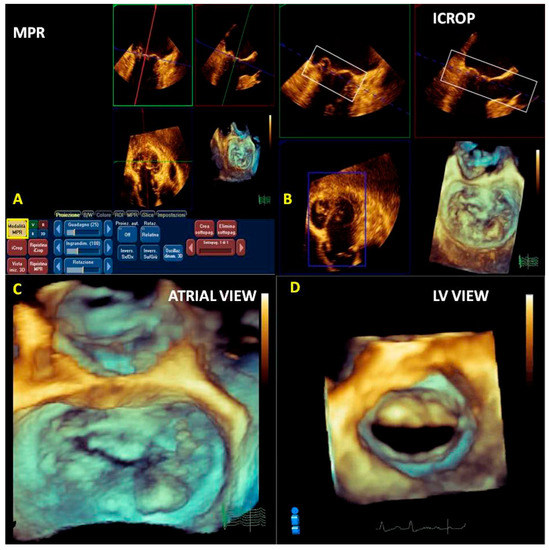

2.4. Post-Processing (Multiplanar Reconstruction and Cropping)